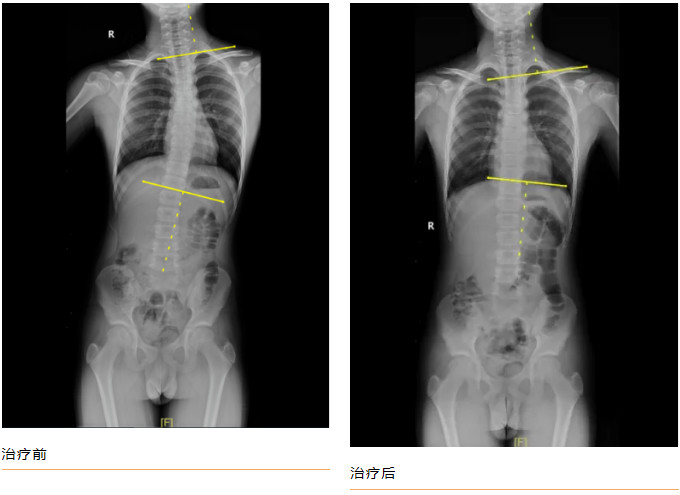

青少年小黄(化名),11岁,家属发现脊柱异常1年余。查体:双下肢真性长度等长,前屈试验阳性,ATR≥5°。全脊柱正侧位片示:“胸椎右侧弯畸形,Cobb角= 23.44 °”。

康复医学科诊疗团队诊断其为“特发性脊柱侧弯”,为小黄制定完善的康复方案:

经过每周3次,共8周的规范治疗后,小黄的脊柱侧弯得到明显矫正,复查全脊柱正侧位片示:“胸椎右侧弯畸形,Cobb角= 13.45 °”